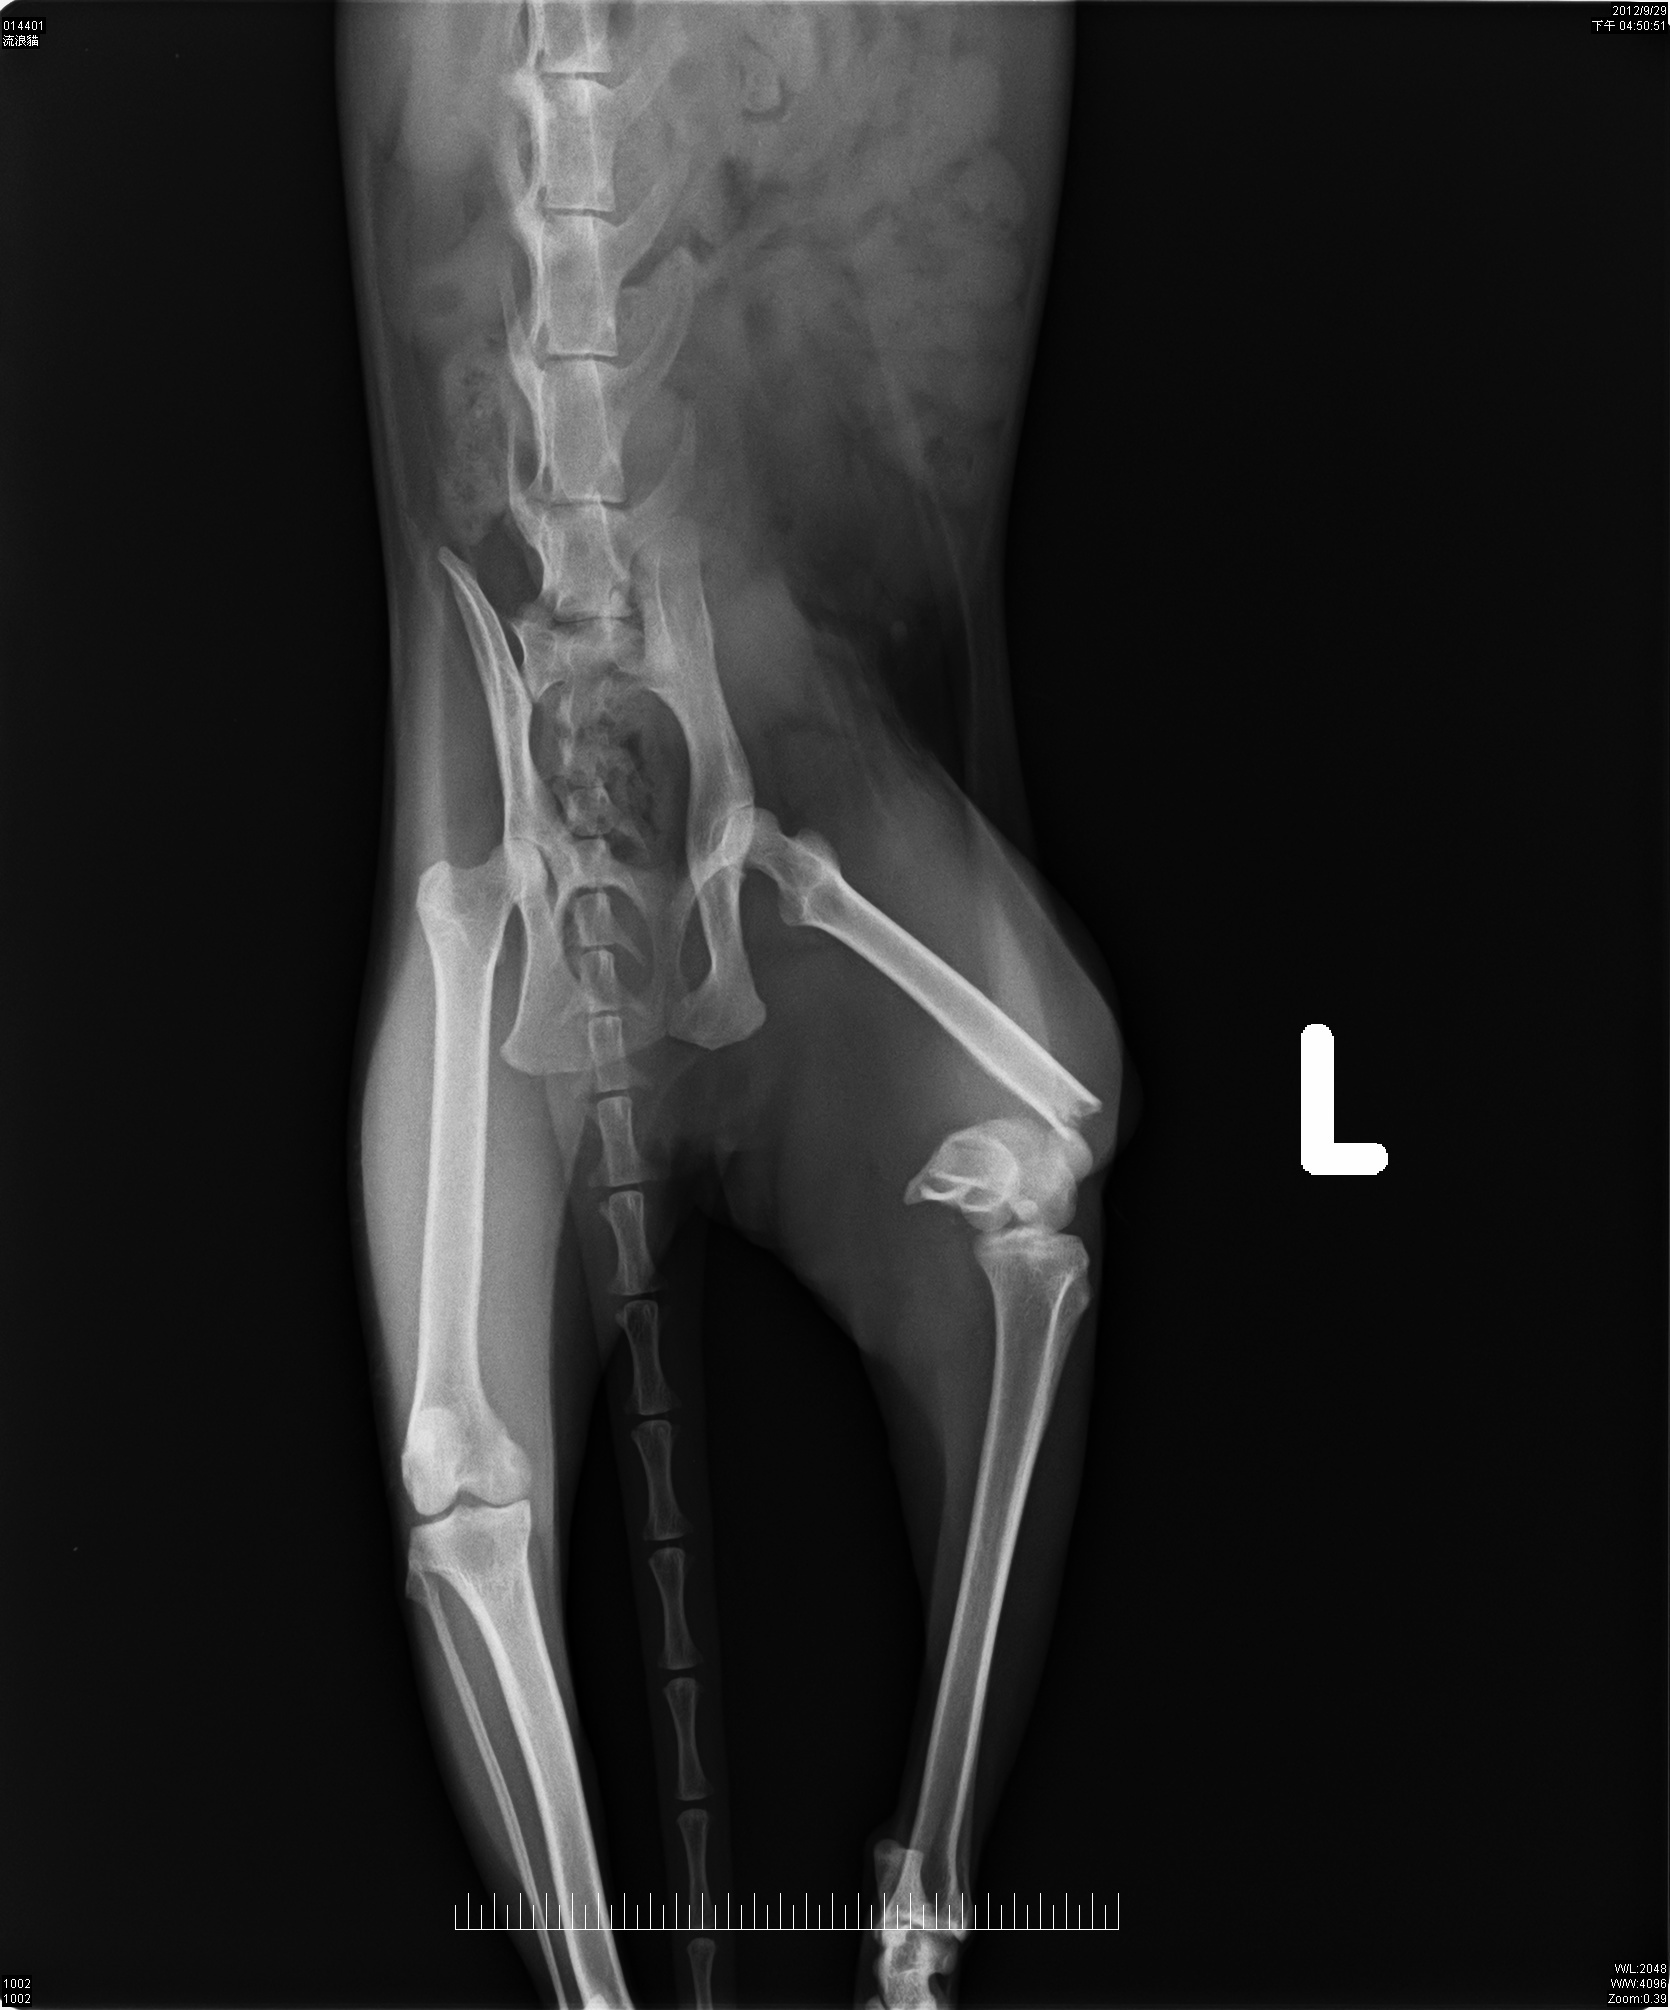

主題: 拖著斷腳討生活的虎斑小女生 申請者姓名: 顧秀雲 花色: 申請日期: 2012-11-19 14:40:17 申請者部落格: 申請者臉書網址: 所在縣市/合作醫院: 高雄市/銀星動物醫院 治療費用: 24500元 需求人數: 26人 已結案 (2013-06-27 14:06:01) 報名人員: Joyce Shih(已付款)、Josie Su(已付款)、Morgan(已付款)、stacy(已付款)、stacy(已付款)、stacy(已付款)、chiawei(已付款)、凌波煙嵐(已付款)、周昱岑(已付款)、尤小慧、Sky(已付款)、Sky(已付款)、Sky(已付款)、Sky(已付款)、Sky(已付款)、Sky(已付款)、Sky(已付款)、Sky(已付款)、Sky(已付款)、Sky(已付款)、Sky(已付款)、Sky(已付款)、Sky(已付款)、Sky(已付款)、Sky(已付款)、Sky(已付款)、潘玥君(已付款)、 候補人員: 動物病情說明: 虎斑妹妹是秀雲姐固定餵養廢棄屋的喵食客之一;消失幾天不見又出現時後腳已經一跛一跛的,一開始秀雲姐先在罐頭裡拌些藥讓虎斑妹妹吃看看,沒想到跛腳的情形沒有好轉...

於是9/29秀雲姐誘捕了虎斑妹妹,一方面是結紮另一方是要治療腳。

在醫院拍了X光片才得知虎斑妹妹的腳斷了,骨頭有粉碎需要開刀並打上鋼釘;但因為虎斑妹妹太瘦弱,所以先做結紮手術後,在醫院休養了幾天再安排手術!!!